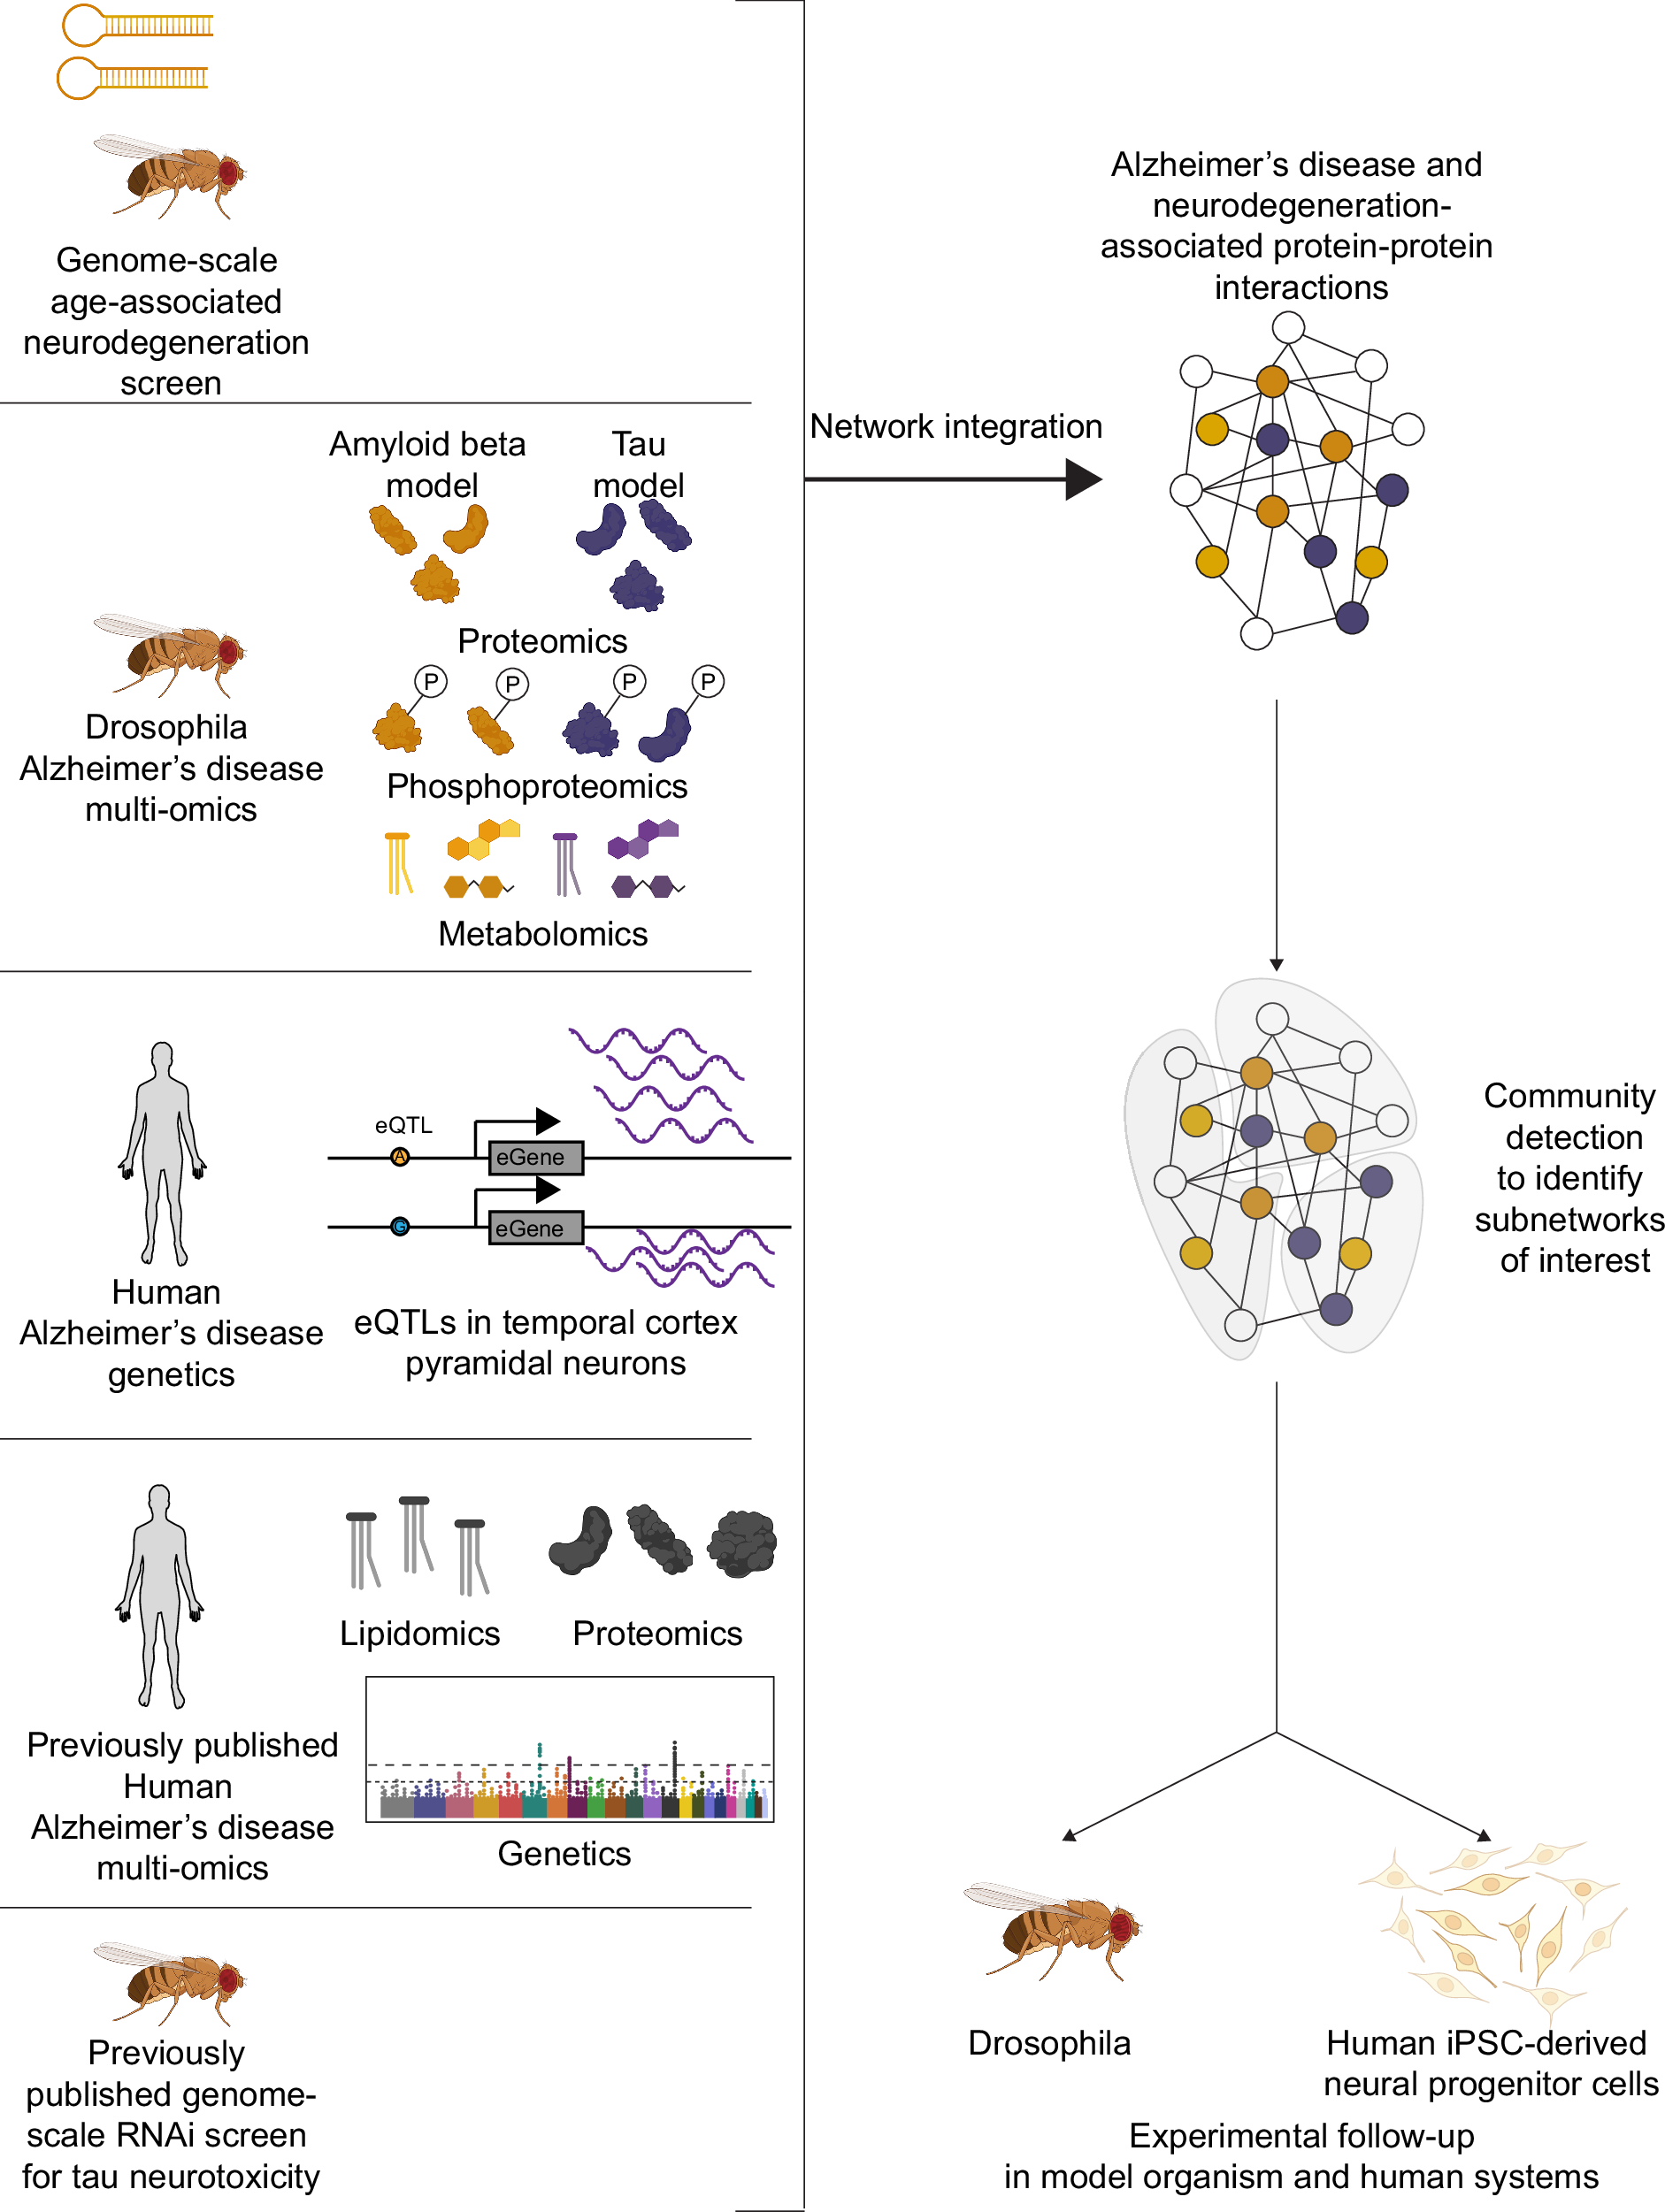

2025-05-20 マサチューセッツ工科大学(MIT)マサチューセッツ工科大学(MIT)の研究チームは、アルツハイマー病の新たな治療標的となる可能性のある遺伝子や細胞経路を特定しました。この研究では、ヒトおよびショウジョウバエのデータを統...